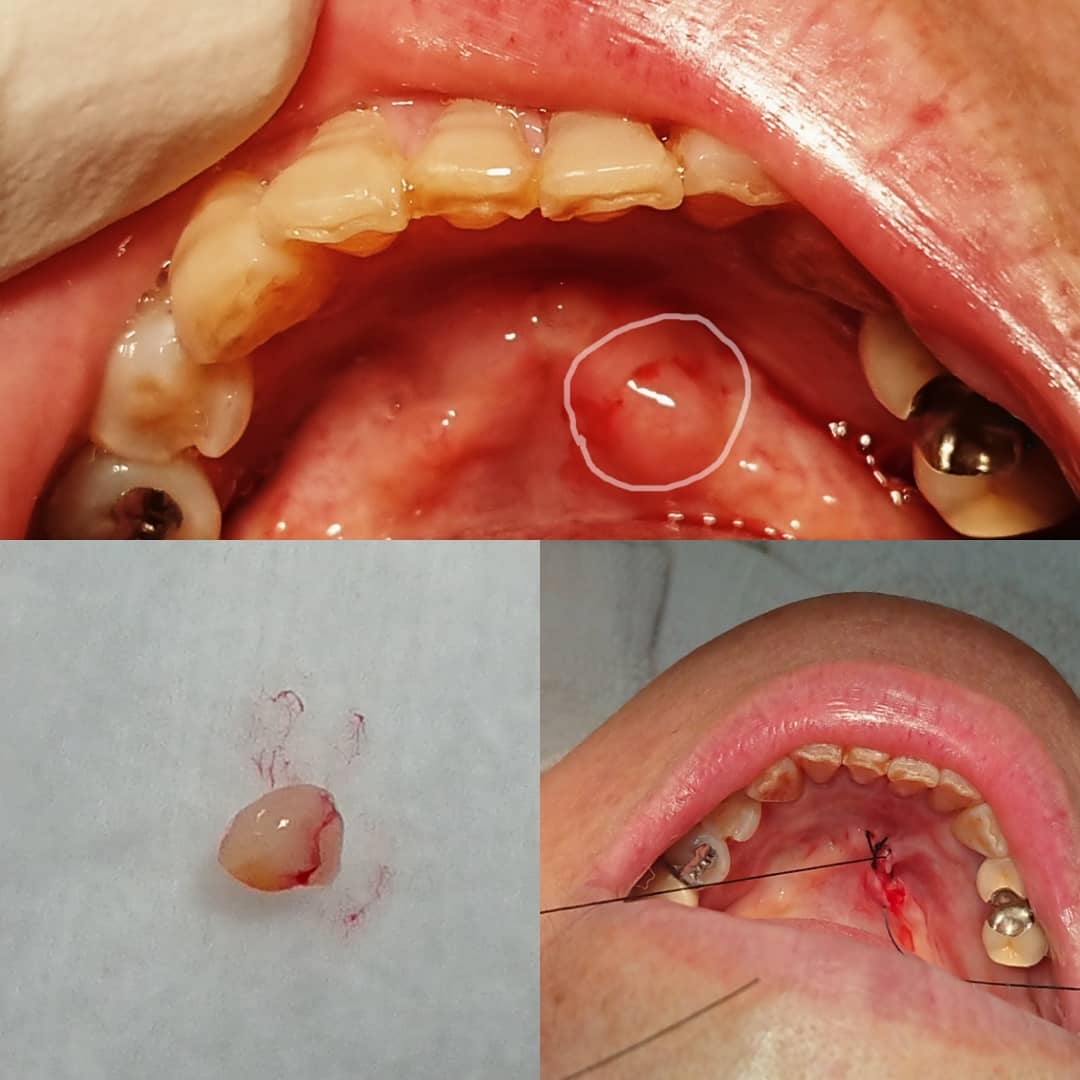

本日の症例は新患さんが上顎に出来物が・・・!

一応ベルスコープにて精査!蛍光ロス

東京歯科大より直ぐに返答!乳頭腫!

【乳頭腫!】

当医院口腔外科歯科医師が次回切除、病理診断を出す予定です!